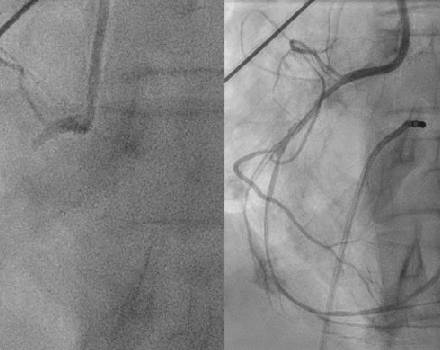

Chronic Total Occlusion of the Coronary Arteries

Chronic total occlusion (CTO) of the coronary arteries refers to the complete blockage of a coronary vessel (100% stenosis), accompanied by the total absence of antegrade blood flow through the artery (TIMI Flow 0), with a duration of more than three months.

Ως χρόνια ολική απόφραξη των στεφανιαίων αγγείων ορίζουμε την ολική απόφραξη του αγγείου (στένωση 100%), η οποία συνοδεύεται από πλήρη εξάλειψη της ορθόδρομης ροής αίματος κατά μήκος του αγγείου (TIMI FLOW 0) που έχει διάρκεια άνω των 3 μηνών.